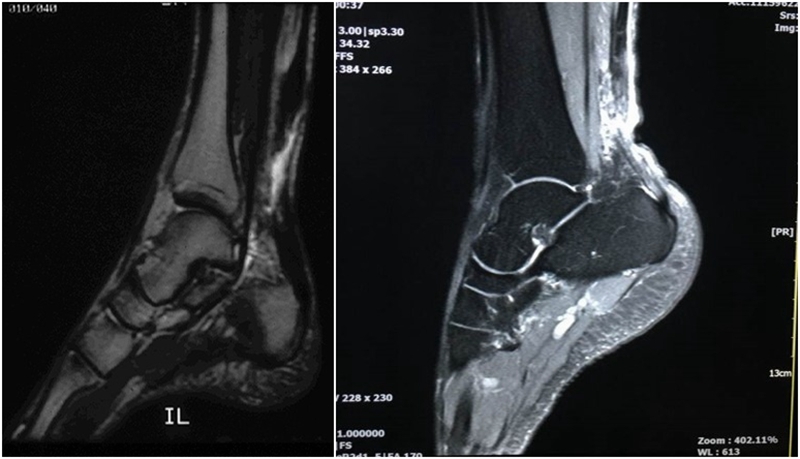

MRI:常用于评估肌肉骨骼的问题,当怀疑跟腱断裂且无高质量诊断性超声可用的情况下是首选检查方法。MRI 在检查跟腱部分撕裂时可以提供更多的解剖细节和更高的准确性。

跟腱撕裂 MRI评价标准:

(1)完全撕裂:跟腱增粗, 腱束分离, 局部T1WI、T2WI信号均匀增高或局部信号不均匀增高, 腱束重叠交织但不连续。

(2)部分撕裂: 跟腱增粗, 局部T1WI、T2WI信号不均匀增高,内见部分连续的腱束影。